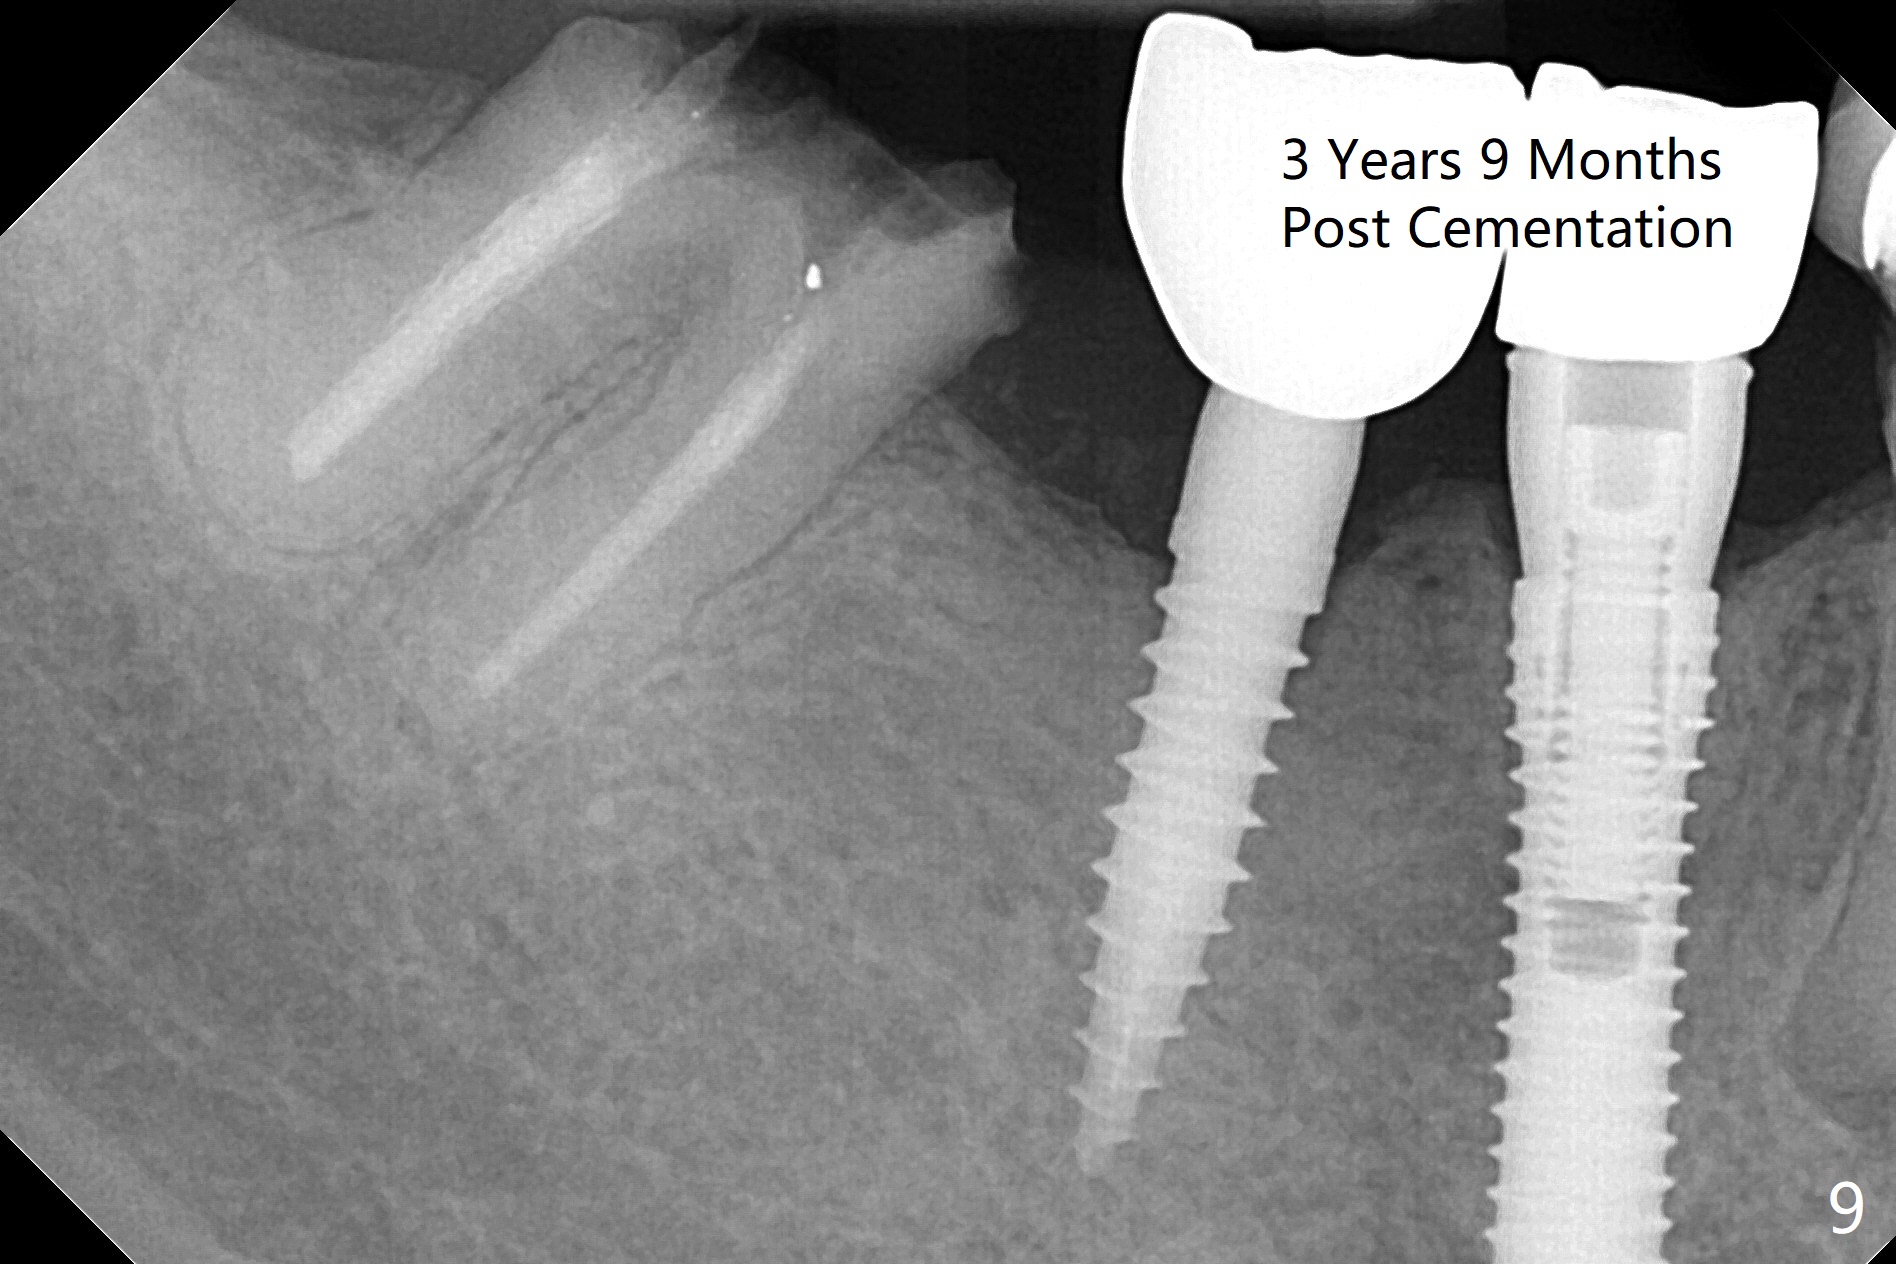

Preop examination shows that the buccal plate at #30 is atrophic (Fig.1 *). The mesiodistal width of the pontic is narrow as compared to the retainer at #31 (Fig.2). It appears that a narrow implant should be placed at #30 and should be able to sustain functional loading. After ridge reduction at #30 (Fig.3 ^) and extraction and debridement at #29, osteotomies at these sites are initiated with 1.2 mm and 2 mm drills, respectively. Probably due to low bone density, the osteotomy at #29 drops deep and close the Mental Loop (red dashed line). While the trajectory at #30 improves, the osteotomy at #29 remains close to the Mental Loop (Fig.4), asymptomatic with infiltration anesthesia. A 3x12(2) mm 1-piece implant is placed at #30 and 3.8x16 mm 2-piece implant at #29 (Fig.5,6 with insertion torque >50 and <50 Ncm, respectively). The large distal defect at #29 (Fig.3,5 *, most likely due to post-related perforation) is later filled with bone graft (data not shown). After placing an abutment at #29 and suturing, periodontal dressing is applied. Three months later, the meisal gap of #29 disappears while the distal one reduces (Fig.7 *). The abutment is changed to 4.5x4(4) mm one before reprep for impression. There is no bone loss 9 months post cementation (Fig.8) or 3 years 9 months post cementation (Fig.9). In fact the crown is lost at #31. At repeated request from the patient, a prefabricated post and crown will be fabricated for short term purpose while an implant is going to be placed at #19. The new crown at #31 has no occlusal contact (Fig.10), which may change over time.